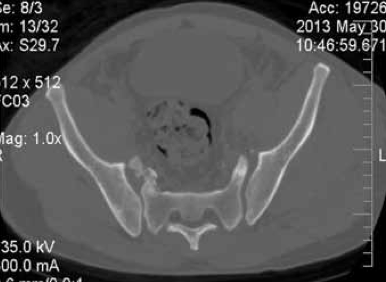

Клинический пример. Пациентка М., 21 год, поступила в клинику через 1,5 месяца после ДТП с диагнозом: ротационно-нестабильное повреждение таза; U-образный перелом крестца с вершиной над SII. Оскольчатый перелом крыла правой подвздошной кости с частичным повреждением правого крестцово-подвздошного сочленения. Радикулопатия S1 справа, S2, S3 с обеих сторон средней степени (Фиг. 1 - обзорная рентгенограмма таза (а); КТ сканы в сагиттальной (б) и горизонтальной (в) плоскости при поступлении).

- фиксация ламинектомированного фрагмента по линии остеотомии сетчатой пластиной (Фиг. 2 - представлена обзорная рентгенограмма таза (а) и КТ сканы в сагиттальной (б) и горизонтальной (в) плоскости после операции. После операции пациентка активизирована на третьи сутки, рана заживлена первичным натяжением, швы сняты не 12 сутки. Проводилась медикаментозная и электоронейростимуляция. Выписана из стационара на 17 сутки после операции.